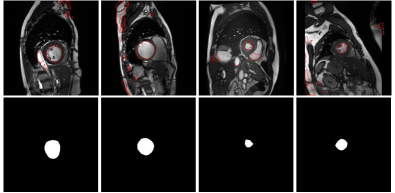

Several failure cases from proposals are depicted in Fig 4. With this strategy, these errors are propagated during training, which might explain the low performance compared to our method. In addition to lower performances, this approach requires to fully train a first model, generate pseudo-labels and then re-train a second model with the generated masks. This contrasts to our method, which is trained in an end-to-end manner.

Refer to caption

Figure 4: Failure cases which are employed as pseudo-labels in the proposals-based approach (top), whose errors are reinforced during training, and their corresponding ground truth. Best viewed in colours.